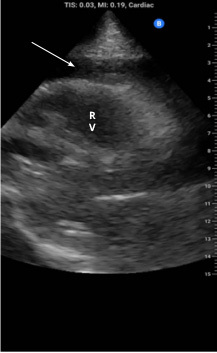

The preferred imaging modality for pericardial injury is transthoracic echocardiography (TTE). It is the first-line modality in suspected cardiac injury because it can rapidly assess hemopericardium and tamponade physiology, including visible right-sided chamber collapse.30 Ideally, cardiac ultrasound can be performed quickly at the bedside, minimally interrupting resuscitation. In the detection of cardiac tamponade, ultrasound has high sensitivity and high specificity, often > 90% when characteristic signs are simultaneously present, particularly right atrium and right ventricular collapse with plethoric inferior vena cava (IVC) and respiratory inflow variation. (See Figure 4.)

Figure 4. Cardiac Ultrasound Demonstrating Pericardial Effusion |

![]() |

Arrow points to the effusion RV: right ventricle Image used with permission from Charles Jang, MD. |